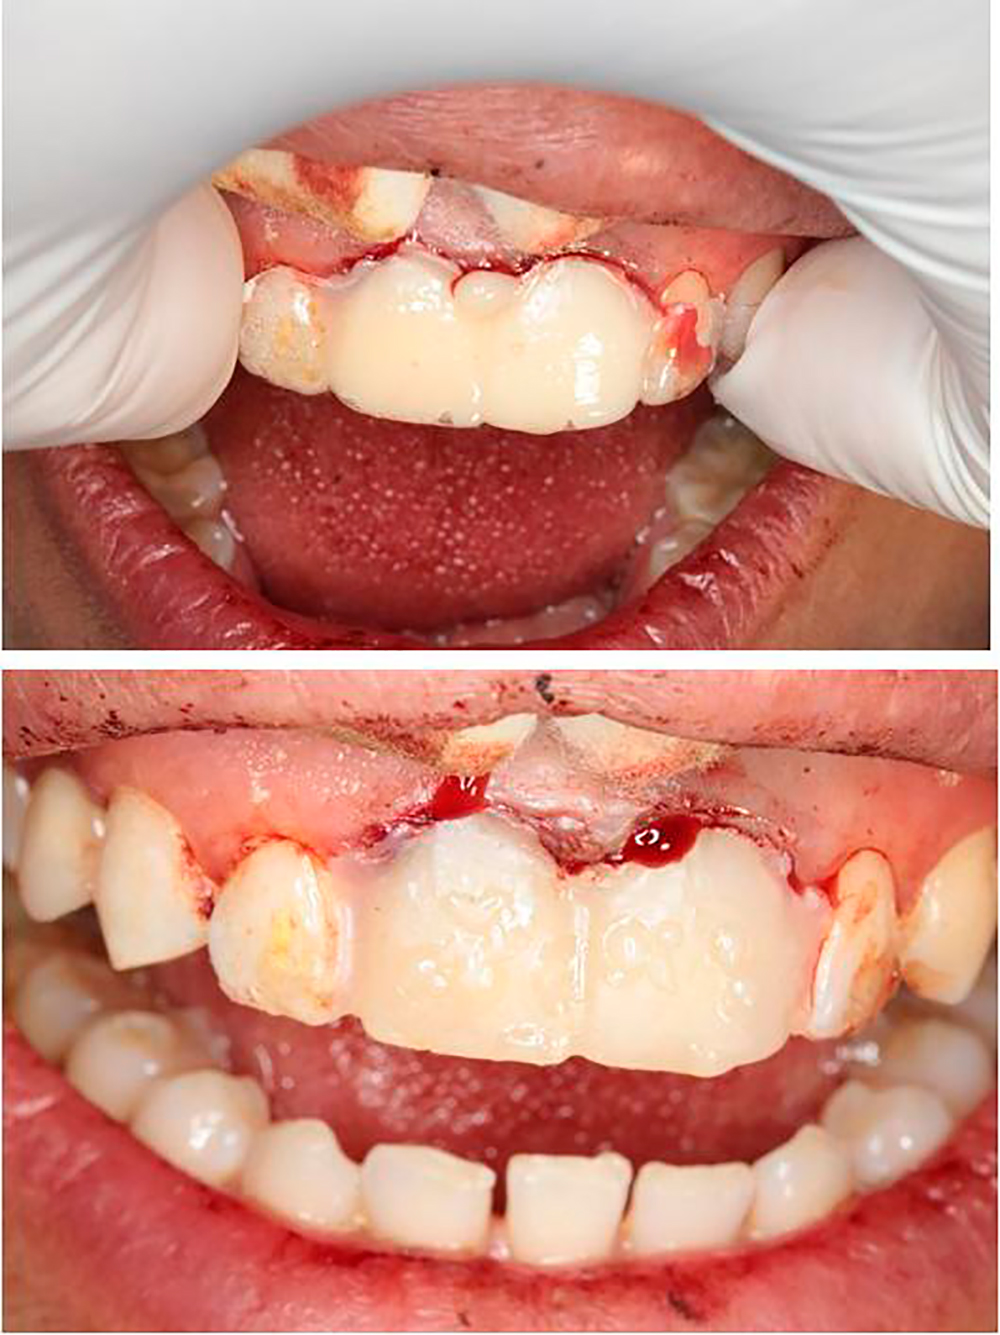

Sleeve fixation and adjustment

Crowns fixation using RFX Cement

Final Stage Of The Restoration